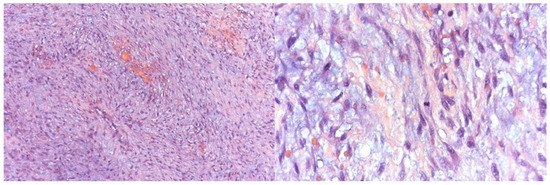

Facelift Approach for Hemimandibulectomy and Costochondral Autologous Graft Reconstruction in a Pediatric Odontogenic Myxoma

Surgeries 2025, 6(4), 102; https://doi.org/10.3390/surgeries6040102 - 20 Nov 2025

Background: Odontogenic myxoma (OM) is a rare, benign, but locally aggressive tumor of odontogenic mesenchymal origin. This study aims to expand current knowledge by integrating a concise literature review with a detailed case report of a surgically complex pediatric OM, treated using a biologically advantageous reconstructive technique. Methods: In this study, we report the case of an eight-year-old girl presenting with a large OM that caused complete disruption of the architecture of the left hemimandible. Due to the tumor’s size and bone involvement, radical resection was necessary. A modified extraoral facelift approach was employed to ensure adequate surgical access while avoiding intraoral incisions and minimizing visible scarring. Immediate mandibular reconstruction was performed using an autologous costochondral graft. Discussion: Although infrequently used in modern surgical practice, the costochondral graft offers unique advantages in pediatric patients due to its inherent growth potential and capacity for long-term biological integration. In this case, the graft allowed restoration of mandibular continuity and form with minimal donor site morbidity, demonstrating its viability even today. Conclusions: This case underlines the importance of tailored reconstructive strategies in pediatric OM. The costochondral graft provided excellent functional and esthetic results, with four-year follow-up confirming stable anatomical remodeling and bone regeneration.